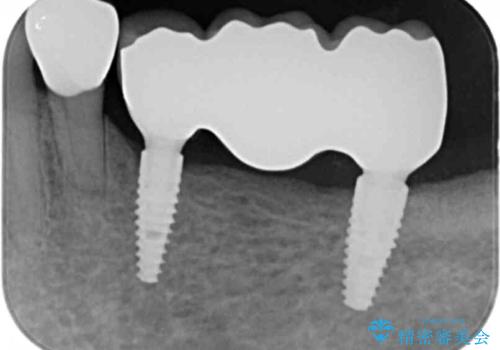

- 113.3万円(インプラント×2・チタンカスタムアバットメント×2・ジルコニアクラウン×3・仮歯×3)費用は治療当時の料金となります

長年使用してきた取り外しの必要な入れ歯と違い、しっかりと噛むことができ取り外しの必要のないインプラント治療で食事をより楽しめるようになりました。